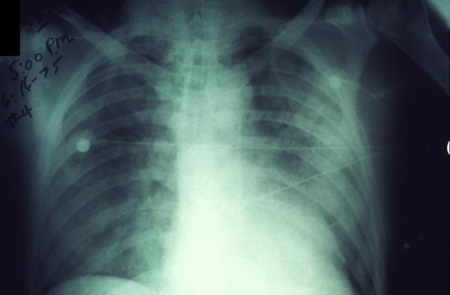

შავი ჭირის ფილტვის ფორმა ორივე ფილტვის დაზიანებით

დაავადებათა კონტროლისა და პრევენციის ცენტრების (CDC) სურათების კოლექციიდან; გამოიყენება ნებართვით.